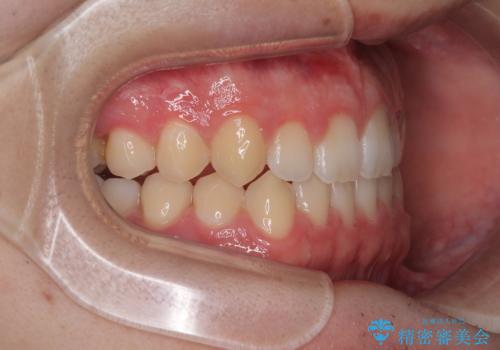

- 「前歯のすきっ歯が気になる」「食べ物が歯の間に詰まりやすい」とのお悩みで来院された20代男性の患者様です。

歯と歯の間に隙間がある**空隙歯列(すきっ歯)**は、見た目の問題だけでなく、食片圧入による歯肉の腫れや、隣接面う蝕のリスク増加につながることがあります。

患者様は「できるだけ目立たない矯正治療」を希望されていたため、インビザラインを用いた治療計画を立案しました。

インビザラインは透明で装着していても気づかれにくく、日常生活やお仕事への影響を最小限に抑えながら治療を進めることが可能です。